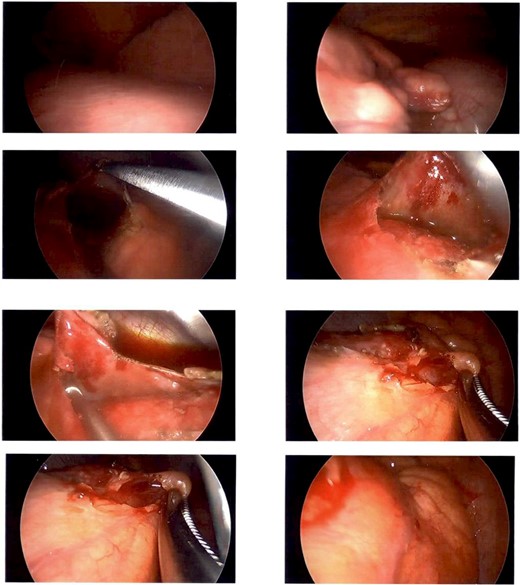

A CT guided biopsy was preformed to attain a diagnosis, which was insufficient for diagnostic purposes. Subsequently a left video-assisted thoracoscopic surgical (VATS) biopsy (Fig. 2), was performed which again was non-diagnostic.

Intraoperative photography from left sided VATs biopsy. Showing a firm cream-coloured nodular and globular intra-pericardial mass containing gelatinous fluid was found circumferentially wrapping the ascending aorta.

A Hemi-sternotomy was performed to re-sample the lesion. A firm cream-coloured nodular and globular intra-pericardial mass containing gelatinous fluid was found circumferentially wrapping the ascending aorta. Thymic tissue looked grossly normal.